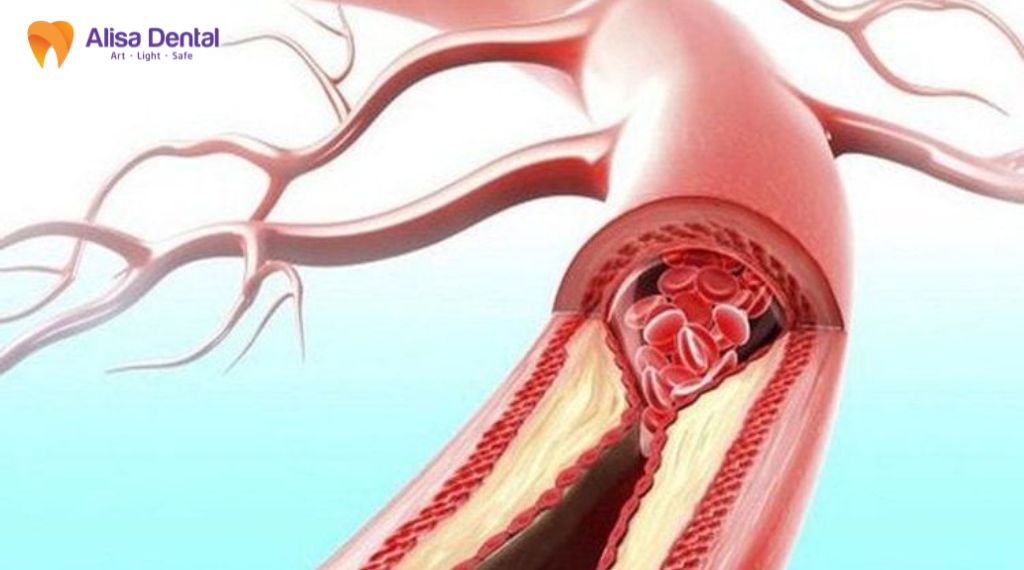

Mô hình viêm hệ thống (Systemic Inflammation)

Khi mô nha chu bị mầm bệnh tấn công, cơ thể sẽ phản ứng bằng cách giải phóng các cytokine viêm như CRP, IL-6, IL-1β và TNF-α vào hệ tuần hoàn. Các chất này khi lưu thông trong hệ tuần hoàn sẽ gây tổn thương lớp nội mạc mạch máu, tạo điều kiện thuận lợi cho việc hình thành mảng xơ vữa. Ngoài ra, tình trạng viêm mạn tính kéo dài có thể góp phần làm tăng nguy cơ bệnh tim mạch và suy tim thông qua cơ chế stress oxy hóa và tổn thương nội mạc mạch máu.

Vi khuẩn từ mảng bám răng, đặc biệt là vi khuẩn “khét tiếng” Porphyromonas gingivalis, có thể xâm nhập trực tiếp vào dòng máu thông qua các vết loét ở nướu khi ăn nhai hoặc đánh răng. Chúng đi xuyên qua lớp nội mạc, gây rối loạn chức năng mạch máu, stress oxy hóa và rối loạn chuyển hóa lipid. Một số nghiên cứu đã phát hiện ADN của vi khuẩn nha chu trong mảng xơ vữa động mạch, cho thấy mối liên hệ sinh học giữa viêm nha chu và bệnh tim mạch.

Một cơ chế quan trọng liên kết viêm nha chu với bệnh tim mạch là hiện tượng molecular mimicry. Protein GroEL/HSP60 của vi khuẩn nha chu có cấu trúc tương đồng với protein HSP60 của tế bào nội mạc mạch máu người. Khi hệ miễn dịch tạo kháng thể chống lại vi khuẩn, các kháng thể này có thể nhận diện nhầm tế bào nội mạc, gây phản ứng viêm mạch máu và thúc đẩy quá trình hình thành xơ vữa động mạch.